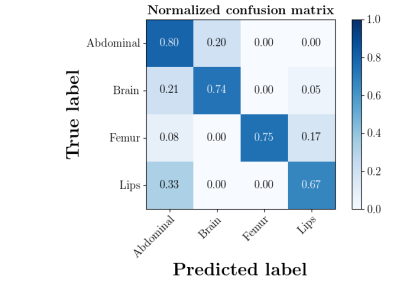

We further compare the performance of MIDNet in a semi-supervised setting and a fully-supervised setting. Here, the semi-supervised setting utilizes the training data containing labeled data and unlabeled data, while the fully supervised setting only uses the labeled data. The confusion matrix in Fig. 14 shows the effectiveness of unlabeled data in our proposed method, for example, the classification accuracy of greatly improves when integrating unlabeled data (semi-supervised).

| With unlabeled data | Without unlabeled data |

|

|